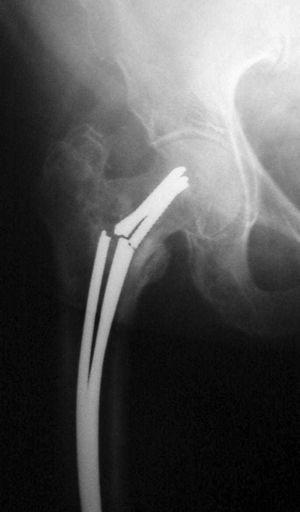

Resultado radiológicoSegún los parámetros de Harper y Walsh 8 , aparecieron 279 casos (75%) de buenas reducciones, 53 casos (14%) en varo y 40 casos (11%) de reducciones en valgo. La colocación de los clavos fue correcta en la proyección AP en 216 pacientes (58%) y en 238 (64%) en la proyección axial, consiguiendo el relleno del canal medular en 234 casos (63%). El tiempo medio de consolidación fue de 11,4 semanas (fig. 2).

Figura 2. Buena consolidación a las 12 semanas de una fractura per subtrocantérea femoral; en la imagen pequeña (abajo a la derecha) se muestra el buen relleno del canal medular.